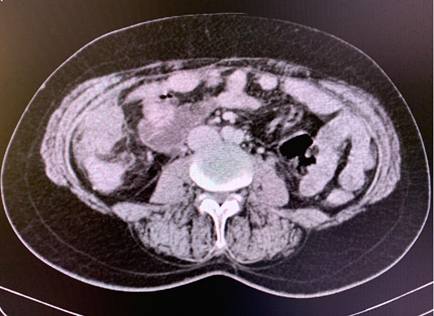

Abdominal ultrasound found a 21mm gallbladder lithiasis with hepatic steatosis. Abdominal CT scan revealed a large heterogenous masse with engulfed gallstones. The patient underwent a cholecystectomy.

The abdomino-pelvic scanner showed peritoneal carcinomatosis secondary to a right ovarian mass without digestive thickening or deep adenopathy and without bone abnormalities. We completed with pelvic ultrasound showing a par-uterine mass measuring 81 mm with great abundance effusion.

The patient received first line chemotherapy based on carboplatin and paclitaxel. After 6 cures she obtained a partial clinical, biological and radiological response (Fgure 1).

The metastatic lesions appear hyper vascularized on the abdominal injected CT scan. In the present case, hypervascularization was objectived with gallstones.